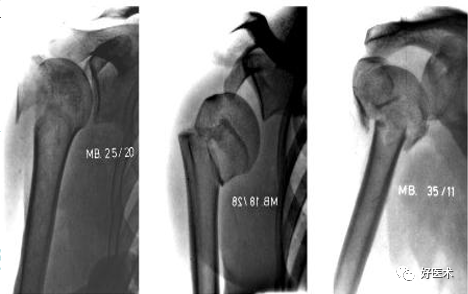

1.Neer分型(基于关节部分和大、小结节和肱骨干的位置关系,骨折块的移位取决于附着肌肉韧带组织的牵拉):

肱骨近端骨折Neer分型

一部分骨折:无移位的肱骨近端骨折,占所有的85%,常见于60岁以上的老年人,常是非手术治疗。三角巾或石膏托悬吊。

二部分骨折:常见外科颈和大结节的撕脱骨折。

三部分骨折:常见为外科颈骨折合并大结节撕脱骨折并移位。肱骨头仍保留良好的血运,主张切开复位内固定。

四部分骨折:

-

软组织损伤严重

血运破坏严重

肱骨头坏死率大

手术并发症多

功能恢复慢

对于60岁以上的老年病人人工肱骨头置换是手术适应征。